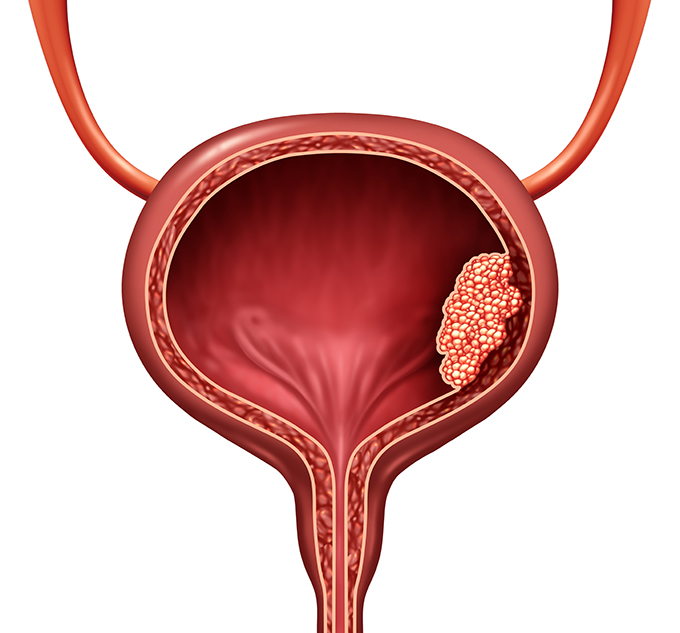

Illustration of different pathological stages of bladder cancer. Stage …

Understanding the Different Types and Forms of Bladder Cancer

Stages of bladder cancer from Meyer et al., (2002). Bladder cancer can …

Overview of staging and grading of bladder cancer tumor. The figure was …

Bladder cancer stages stock illustration. Illustration of inside – 10332948

Bladder Cancer Staging | MedicineBTG.com